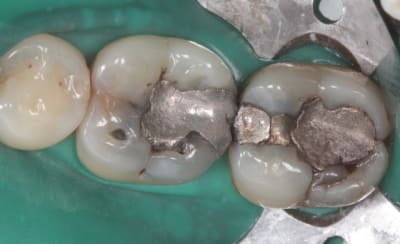

ca parait encore carié sur les photos :-(

tu controles avec quoi pour faire la différence entre coloré et carié ?

je vérifie à la sonde, et je travaille sous loupe 3.6.

Mais je suis d'accord avec toi cela fait souvent cet effet en photo. On arrive à un grossissement plus important qu'avec les loupes, et on voit mieux sur la photo. Pas impossible que j'ai laissé des zones atteintes.

Elles seront fermées hermétiquement sous la résine. C'est que je me dis pour m'endormir ;)

Pour la 7 ça sera un substitut dentinaire (comme on dit) et un onlay labo.